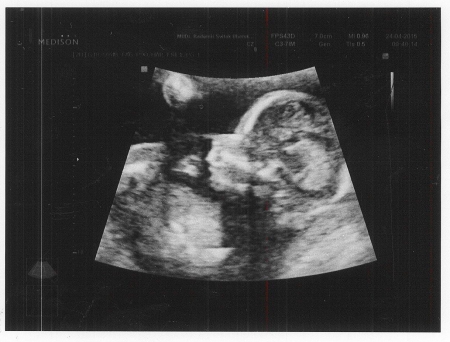

V tomto období těhotenství plod rychle roste, výrazně se prodlužují dolní končetiny, takže tělní proporce jsou již dost vyrovnané a podobají se v podstatě proporcím mezi jednotlivými částmi těla při narození. Plod končetinami čile pohybuje. Při vyšetření ultrazvukem jej často nachytáme, jak si cucá paleček na ruce nebo dokonce na noze.

Plod měří v 17. týdnu těhotenství od temene k zadečku 11 - 12 cm a váží 90 - 100 g.

U maminek v druhém trimestru se zesiluje pigmentace kůže, může se objevit střední čára pod pupkem, ztmavnout prsní dvorce, zvýraznit znaménka, objevit se pigmentové skvrny v obličeji. Po porodu pigmentace ustupuje. Je však vhodné se v těhotenství chránit kvalitními opalovacími prostředky, zvětšující se bříško rozhodně nevystavujeme přímému působení slunečních paprsků. Šetrnější jsou opalovací krémy s minerálními filtry místo chemických. Nejedné ženě se na kůži objeví pavoučkový névus – červená pavučina. Dá se odstranit laserem po porodu, mnohým spontánně vymizí. Část budoucích maminek trápí v tomto období zácpa. Její největší prevencí je dostatek vlákniny a tekutin, rovněž pravidelný stravovací režim. U miminka probíhá vývoj ve všech směrech, na ultrazvuku vznikají v tomto období nejkrásnější snímky typu: cucající paleček, zívající miminko, zdravící miminko apod. Maminka čilé pohyby miminka stále pro dostatek plodové vody v děloze necítí. JM